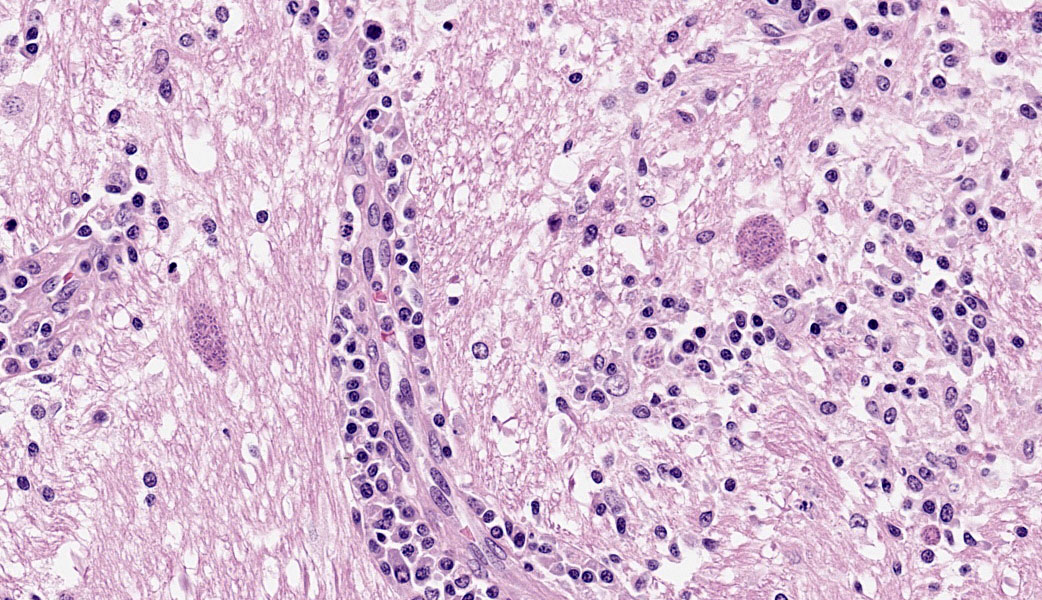

Brain: The meninges are moderately expanded by macrophages, plasma cells, and lymphocytes that surround and partially obscure reactive meningeal vessels. Inflammatory cells extend around vessels into the subtending parenchyma, filling and expanding Virchow Robin spaces up to 12-15 cell layers thick. There are focal areas of infiltration of macrophages, lymphocytes, and plasma cells into the surrounding parenchyma with associated vacuolation and necrosis of the parenchyma, neuronal satellitosis and necrosis, infiltration of gitter cells, gliosis, and astrocytosis. Isolated within the parenchyma and associated with areas of inflammation and necrosis are numerous 12 to 45-µm diameter protozoal cysts containing closely packed clusters of 1 to 2-µm wide, crescent-shaped bradyzoites. At the level of the corpus striatum, there is vacuolation of white matter tracts with occasional spheroids, digestion chambers, and numerous protozoa. Vessels adjacent to the lateral ventricle are obscured by macrophages, lymphocytes, plasma cells, and neutrophils with indistinct, hypereosinophilic vascular walls (necrosis) and perivascular exudation of fibrin and edema. The ependyma spanning the lateral ventricle is segmentally discontinuous with disruption by inflammatory cells and necrotic material that extend into the ventricular lumen.

Brain: Meningoencephalitis and ventriculitis, necrotizing and histiocytic to lymphoplasmacytic, subacute, multifocal, moderate, with protozoal cysts and zoites, vasculitis and vascular necrosis.

Cerebrum: Meningoencephalitis, necrotizing and lymphohistiocytic, subacute, multifocal to coalescing, marked, with vasculitis and apicomplexan cysts.